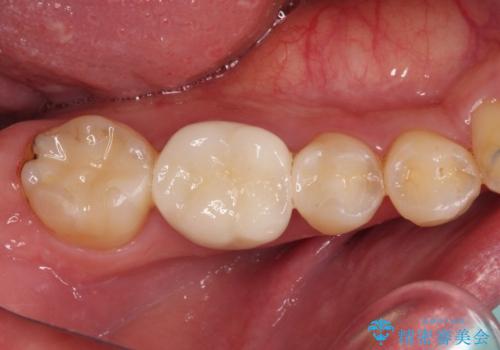

奥歯には目立つ銀歯が多くあるので、矯正治療後には下顎の銀歯をセラミッククラウンやセラミックインレーにより、補綴・修復治療することとしました。